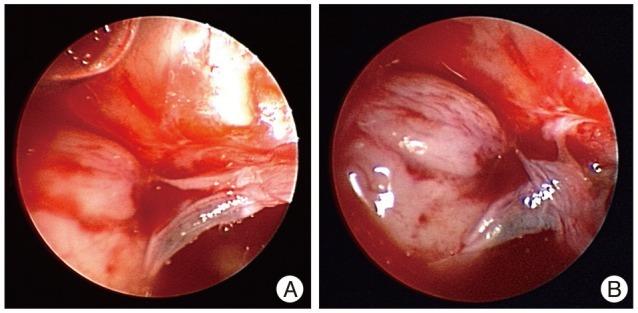

We report an uncommon case of a 45-year-old woman who presented with spontaneous rhinorrhea. A computed tomography (CT) scan of the head revealed an abnormally large sphenoid sinus associated with a parasellar bony defect (Sternberg's canal) through which magnetic resonance imaging could detect an encephalocele of the right temporal lobe. An endoscope-assisted trans-sphenoidal approach was performed and, with the aid of image guided surgery, reduction of the encephalocele was obtained and followed by surgical repair of the dural and bony defects. The postoperative course was uneventful and the cerebrospinal fluid fistula was closed as confirmed by the postoperative CT scan and by the absence of rhinorrhea. After three years of monitoring the patient remained asymptomatic.

我们报告了一例罕见病例,一名45岁女性出现自发性鼻漏。头部计算机断层扫描(CT)显示蝶窦异常增大,并伴有鞍旁骨质缺损(施特恩贝格管),通过该缺损磁共振成像可检测到右侧颞叶脑膨出。采用内镜辅助经蝶窦入路,并在图像引导手术的辅助下,成功将脑膨出复位,随后对硬脑膜和骨质缺损进行了手术修复。术后过程顺利,术后CT扫描及无鼻漏证实脑脊液瘘已闭合。经过三年的随访,患者仍无症状。